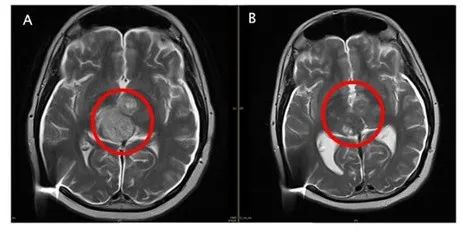

图A:入组前核磁影像,红圈内显示有大量的弥漫性病灶。

图B:ACT001单药治疗后影像,肿瘤细胞密度大幅降低。

据报道,ACT001于2016年获得澳大利亚临床伦理批准,2016年9月19日迎来第一位自愿服用的澳洲患者,至今已有数名GBM患者参与临床试用。2017年3月,一位澳洲复发GBM患者,加入澳洲临床试验,入组时颅内瘤体大小接近4厘米,经过ACT001单药长期治疗,2018年10月达到完全缓解。截至目前,该患者已用药超过50个月,依然是完全缓解状态。